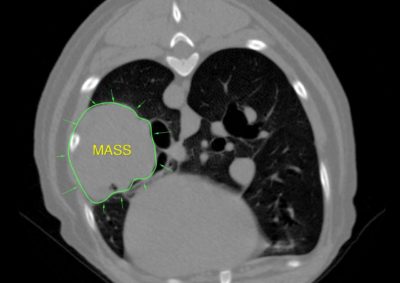

腫瘍外科 注意 ボタンをクリックした先に、治療中および手術中の画像が説明で使用されている場合がございます。 そのような画像に弱い方は閲覧なさらないようお願いいたします。 腫瘍外科 犬の甲状腺癌 軟部組織外科腫瘍外科 唾液腺癌 Salivary gland carcinoma 軟部組織外科腫瘍外科 胃部分切除術・ビルロートI 腫瘍外科 MLO 多小葉性骨腫瘍 腫瘍外科 軟部組織肉腫 G3 軟部組織外科腫瘍外科 直腸プルスルー 内科腫瘍外科 尾状葉乳頭突起に限局した高分化型肝細胞癌 内科腫瘍外科 猫の消化管型リンパ腫(腸穿孔を伴う) 腫瘍外科救急・集中治療 腹腔内出血 内科腫瘍外科救急・集中治療 細菌性腹膜炎 腫瘍外科 肝臓原発血管肉腫 腫瘍外科 犬の原発生肺癌(左) <1234567> 症例カテゴリー 放射線治療整形外科軟部組織外科脳神経外科内科腫瘍外科救急・集中治療リハビリテーション科腫瘍内科内視鏡科脳神経科呼吸器外科中医・漢方猫の腎移植循環器科